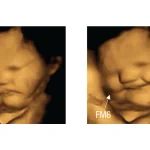

赤ちゃんはおなかの中で、母親の食べたものの味に反応していた!

おもしろ・笑える|5.4万 8407